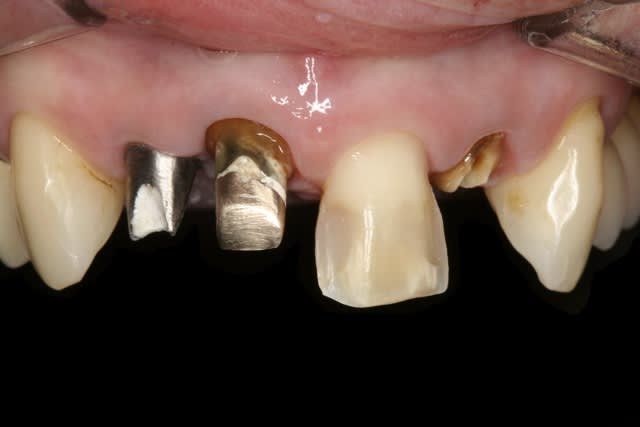

La demande concerne la réhabilitation esthétique du bloc incisif supérieur.

On ne parlera pas de bruxisme, de dvo, de gouttière et de réhabilitation globale pour diverses raisons, seule le traitement esthétique de 14 a 24 nous concerne ici et ses différentes solutions pour le traiter.

A part 24 rien ne bouge, pas de douleurs, pas de problème paro, juste un problème esthétique sur ses vielles ccm.

on fait juste des nouvelles ccm ou on peut faire mieux?